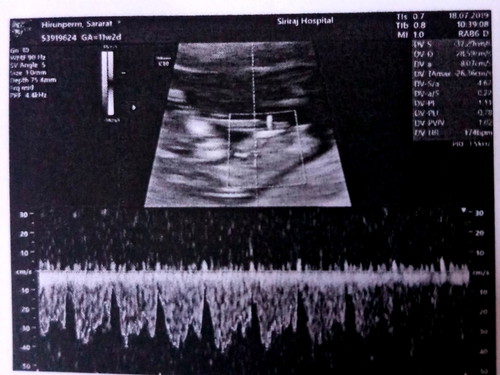

จากเมื่อตอน 5 วีค ซาวนด์แล้วไม่เห็นอะไรเลย หมอพูดสะแม่ใจไม่ดี แต่พยายามไม่คิดมาก บำรุงตัวเองต่อไป วันนี้ 11 วีค 2 วัน ได้ซาวนด์จริงจังครั้งแรก เห็นลูกแล้วค่ะ น้องปกติดีทุกอย่าง ได้ยินเสียงหัวใจแล้วน้ำตาคลอเลย ❤ ขอให้แม่ ๆ ทุกคน ที่ยังไม่เห็นลูกตอนอายุครรภ์น้อย ๆ ทำใจให้สบายนะคะ บำรุงตัวเองต่อไป รออายุครรภ์ที่เยอะขึ้น ยังไงก็เห็นลูกแน่นอนค่ะ ? (รูปสุดท้ายคือตอนซาวนด์ 5 วีค)